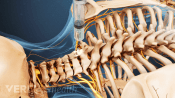

Injections relieve neck and back pain by delivering medications directly to the affected area, reducing inflammation.